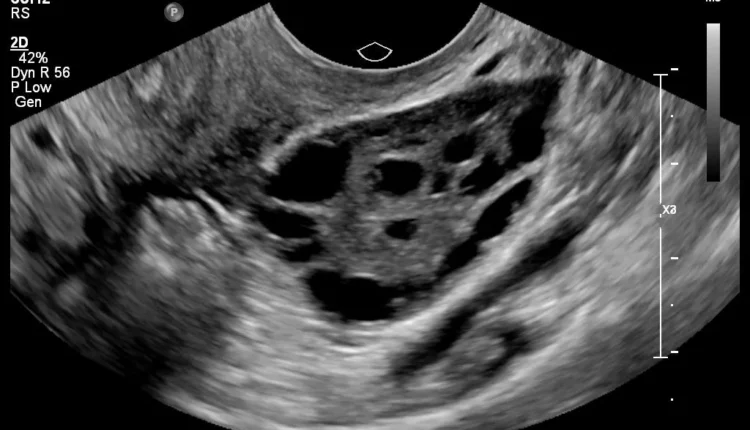

• أكياس صغيرة على المبايض تظهر عادة بالموجات فوق الصوتية

3. الموجات فوق الصوتية: فحص المبايض